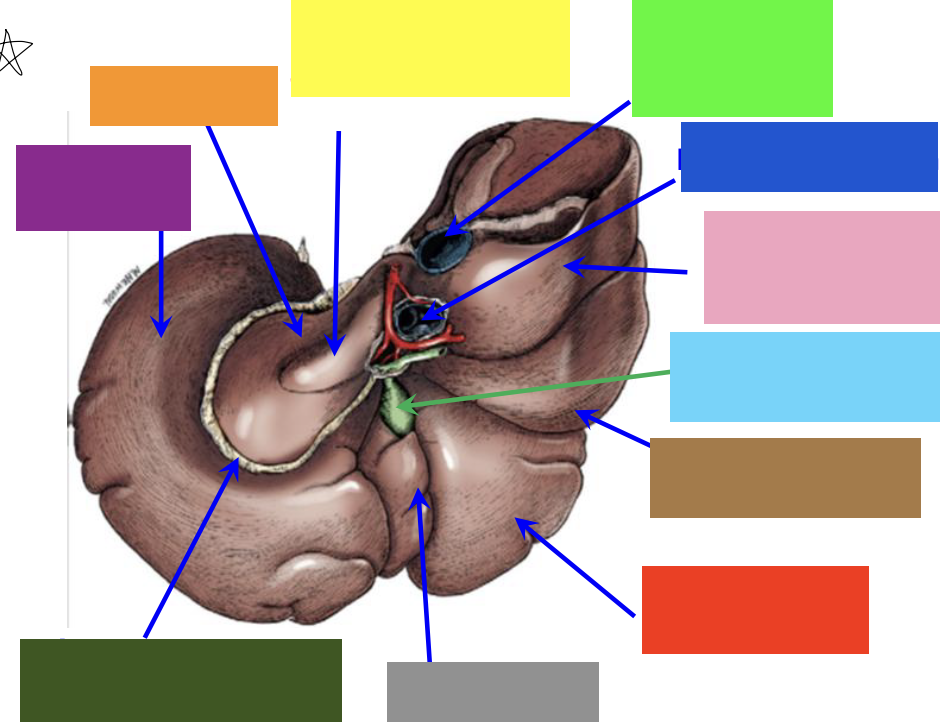

blue box

right triangular ligament

green box

right lateral lobe

purple box

coronary ligament

pink box

right medial lobe

yellow box

left medial lobe

orange box

left triangular ligament

brown box

left lateral lobe